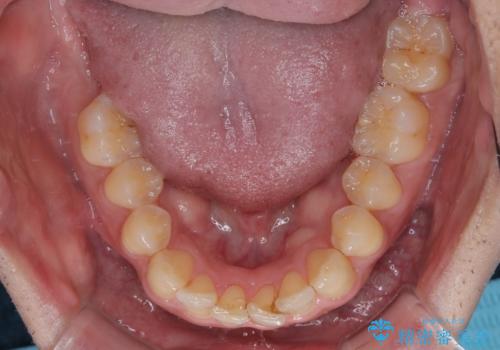

- 上下前歯のデコボコを気にして来院された患者様です。

ワイヤー矯正でもマウスピース矯正でも可能でしたが、短期間で、自身の手を煩わせることなく治療を行いたいとのことで、ワイヤー装置にて矯正治療を行うこととしました。

上顎前歯の舌側転位が顕著であったため、治療期間が長くなると思われましたが、僅か1年で無事に終えることができました。